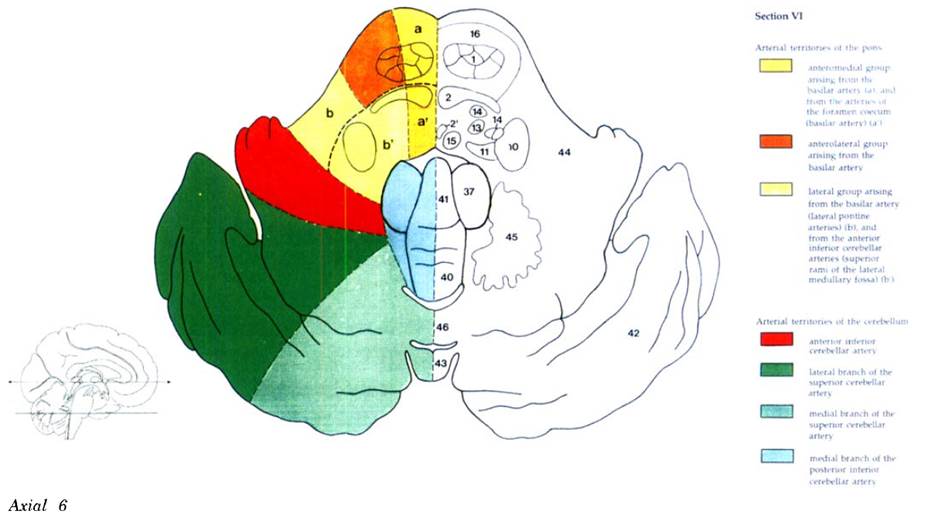

Cerebral vascular territories

Brainstem